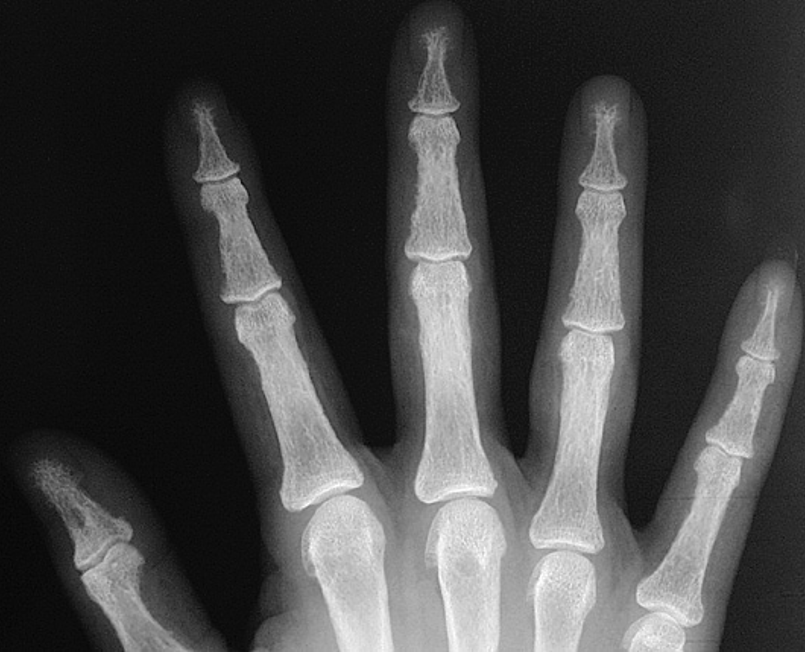

Acro-osteolysis

Definition

Absorption of distal tuft of phalanx

DDx

Psoriasis

Scleroderma / Raynauds

Frost Bite

Hyperparathyroidism

Diabetes

Vasculitis

Leprosy

RA rarely

Gout